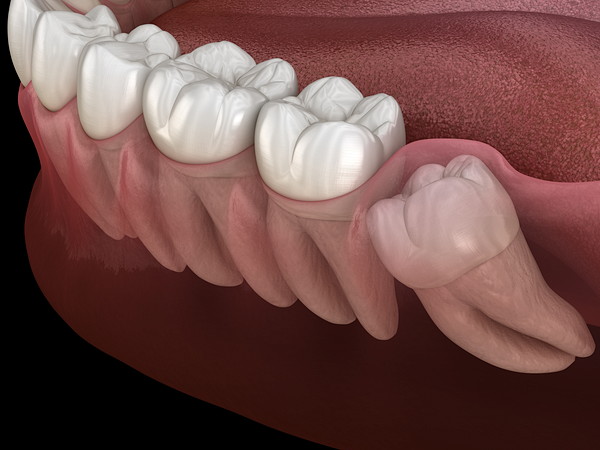

その結果、斜めに生えることや、真横に生えてほかの歯を押し、歯並びに悪影響を与えることがあります。

最後に生えてくるため、歯が生えるスペースが足りないことが多く、「斜めに生える」「歯ぐきに半分被った状態」「真横に生えている」などのケースがあります。

斜めに生えているタイプ

まっすぐに生えていないため、歯磨きの際にも歯ブラシが当たっているか確認しにくく、汚れが残りやすいタイプです。

このタイプは歯ブラシが当たりにくいことから、磨き残しがたまり、虫歯や歯周病のリスクが高いといわれています。

横向きに生えていた親知らずを放置していたため、隣の歯が虫歯になることもあります。

親知らずが斜めに生えていることで、隣の歯との間にプラークがたまり、虫歯につながります。

このような場合には、早めに親知らずを抜歯することがおすすめです。

また、親知らずが正常に生えていないと、隣の歯を押して歯並びに悪影響を及ぼすこともあります。